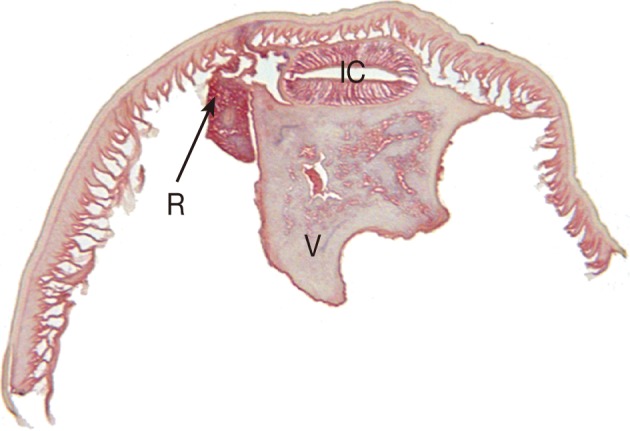

The intestinal cecum, confirmed by section of the anterior part of the worm, was 1.1 mm in length, stretching to the middle level of the ventriculus. The tail, 0.20 mm in length, was conical with a terminal mucron. The presence of an intestinal cecum without ventricular appendage was easily observed in the transverse section of the worm (Fig. 2). All of these findings readily identified the specimen as a third stage larva of Pseudoterranova decipiens. After removal of the larva, the patient returned home and followed up uneventfully.

The most important structure of anisakid larvae in species identification is their esophagointestinal morphologies with the corresponding measurements. Anisakis spp. larvae have a simple and straight arranged digestive tract, i.e., muscular esophagus, ventriculus, and intestine. On the other hand, in Pseudoterranova spp. larvae, the presence of an intestinal cecum without ventricular appendage is the key to distinguish from Contracecum spp. larvae [5]. The present worm could be diagnosed as a third stage larva in consideration of the fact that the cecum reached beyond the one-third level of the ventriculus anteriorly, along with the presence of a mucron at the posterior end [5].